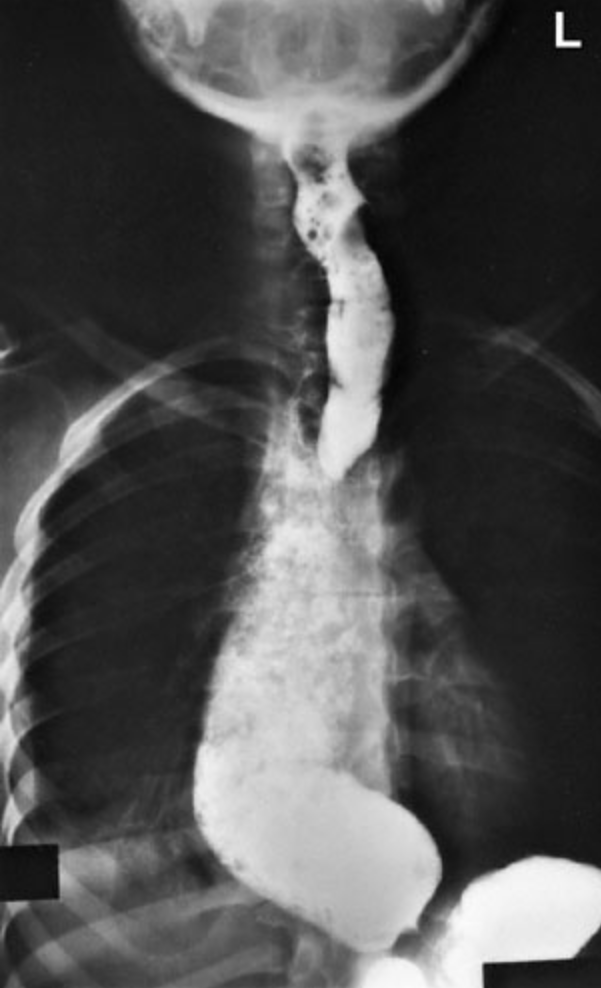

15. Question

A previously healthy 52-year-old man comes to the physician because of a 6-month history of difficulty swallowing solids and liquids. He has had a 2.3-kg (5-lb) weight loss during this period. Examination shows no abnormalities. An upper gastrointestinal series with barium contrast is shown. Which of the following is the most likely diagnosis?